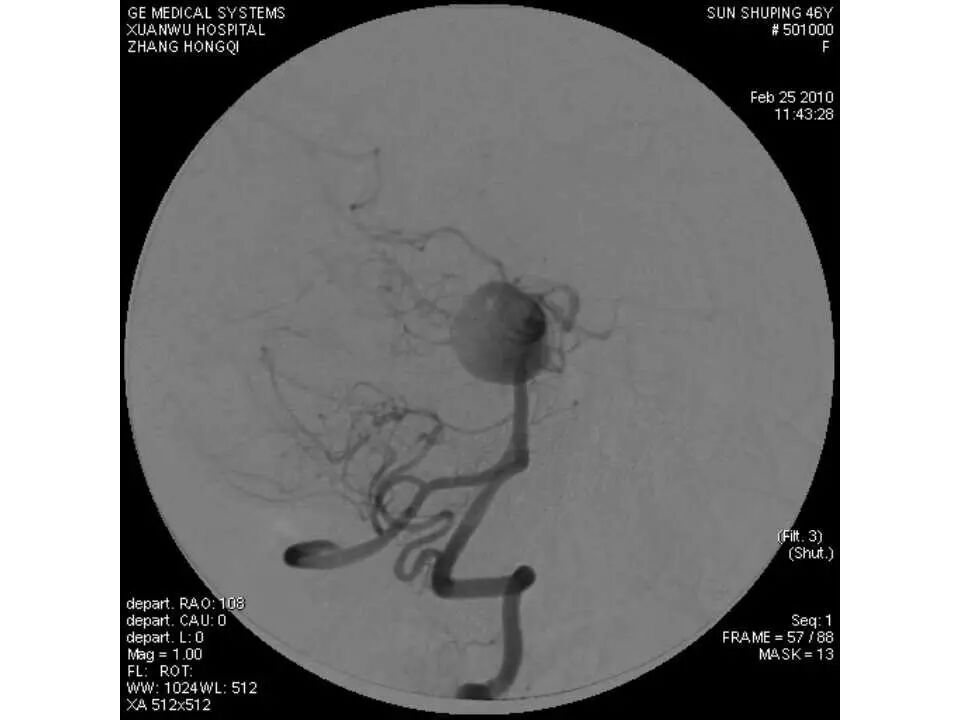

今天为大家分享的是“强生医疗CNV-神经介入专栏”第十五期,由首都医科大学宣武医院何川教授带来的“颅内动脉瘤介入治疗”精彩讲课视频及PPT,欢迎观看、阅读。文章仅代表作者个人观点,如有不同见解,欢迎同道斧正!

何川 ,首都医科大学宣武医院副主任医师,中国医师协会神经介入专业委员会常务委员,长期从事脑血管病和脊髓血管病的手术及介入治疗和相关研究工作。首都医科大学神经外科博士,师从于中国神经介入开创人凌锋教授;日本东北大学医院脑血管病治疗科博士后,师从于日本国脑血管病血管内治疗的开创者高桥教授。